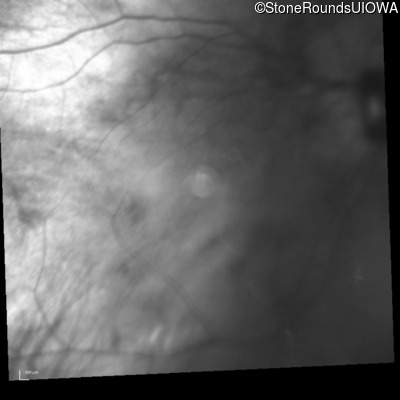

Infrared Fundus Photograph - Right - 20/40 +2

Exemplar